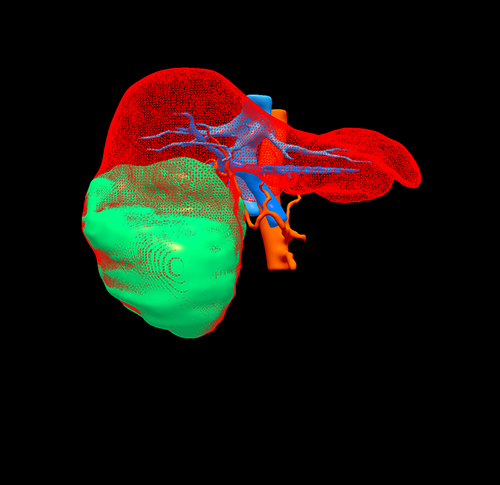

右肝巨大肝癌---右半肝切除